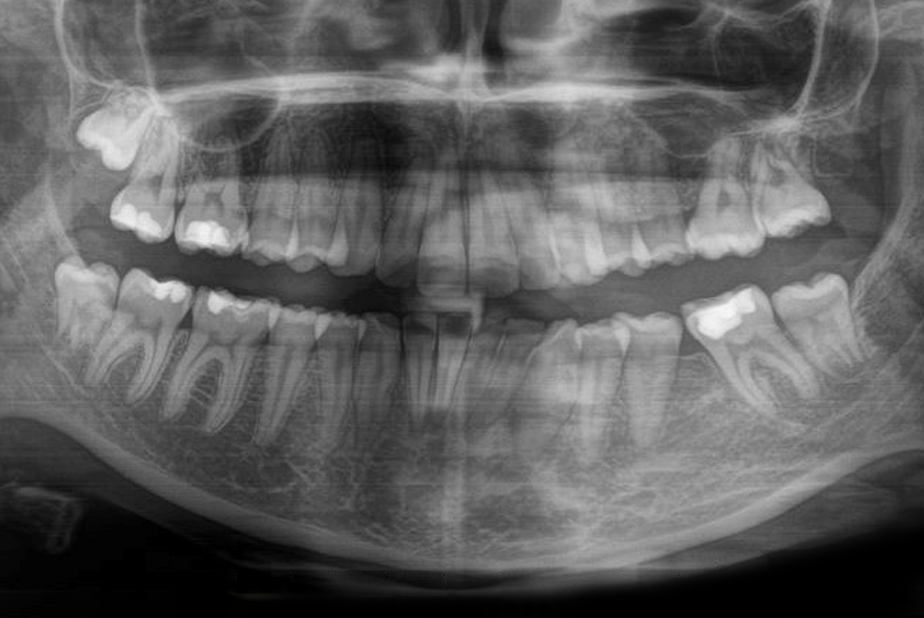

Ortopanoramica post-trattamento che mostra la chiusura degli spazi estrattivi

Fig. 7 Ortopanoramica post-trattamento che mostra la chiusura degli spazi estrattivi